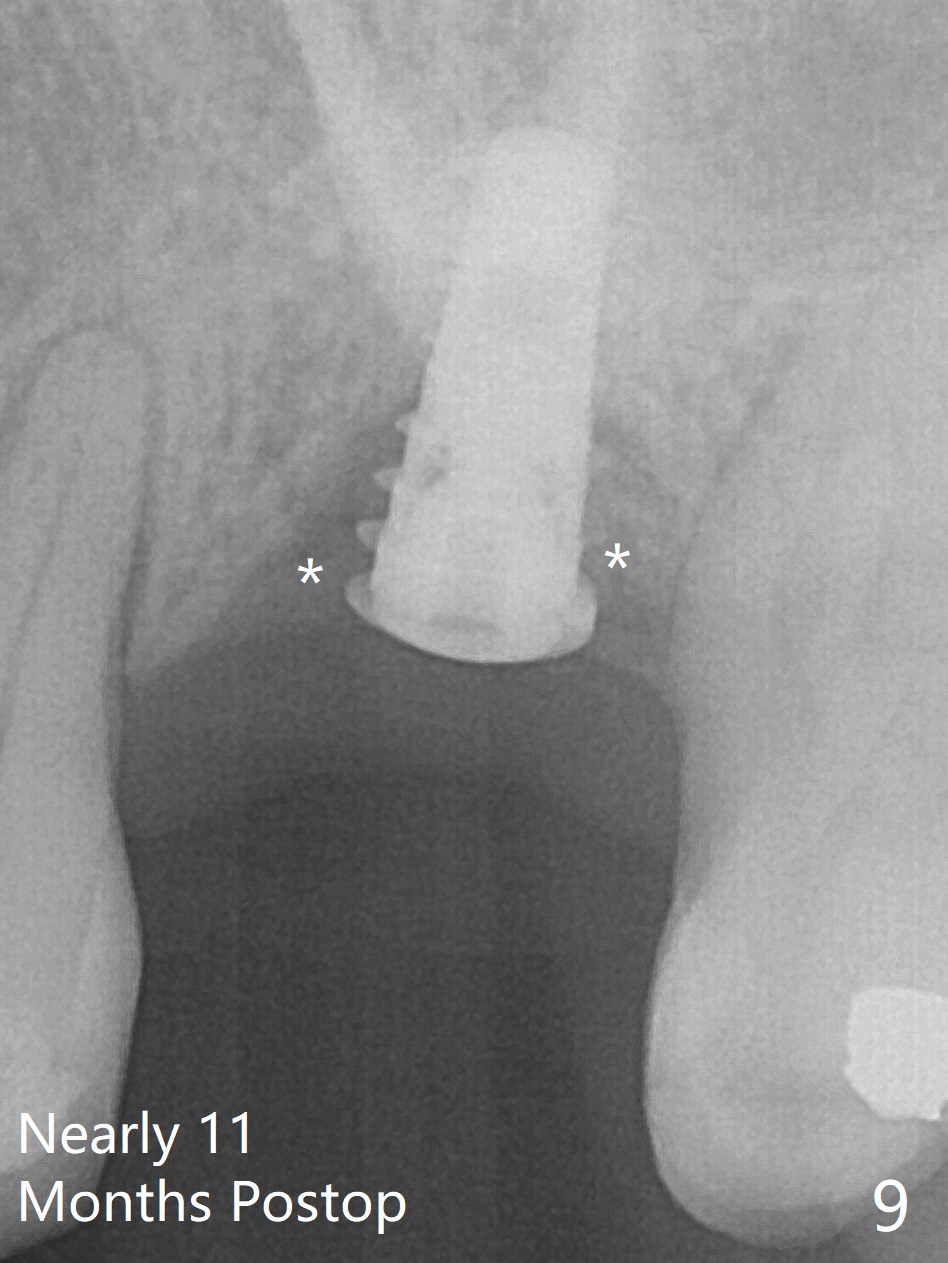

Preop exam shows the narrow ridge at #14. Magic split is used for access and initiation of osteotomy and bone expansion, followed by 3 mm Magic Expander for 11 mm (ME, Fig.1 (yellow line: sinus floor)). In fact the bone is soft. After use of 3.8 mm ME and Lindamann bur (to move the osteotomy distobuccally), a 4x11 mm dummy implant is placed with 20 Ncm (Fig.2). Following use of Lindamann bur for the same purpose as mentioned above, a 4.5x9 mm IBS implant is placed 3 mm subgingival with <30 Ncm (Fig.3,4). Bone graft is placed for sinus lift prior to implantation. A 5x3 mm healing abutment is placed. Bone loss is minimal 3.5 months postop (Fig.5) and striking 8 months postop (after crown cementation, Fig.6-8). The bone loss persists in spite of crown and abutment removal (Fig.9,10). Bone graft or implant redo is planned.